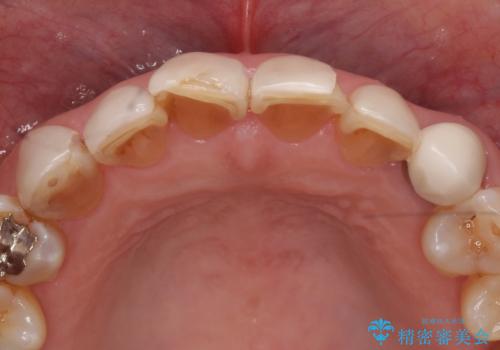

- 前歯の色や形を全体的に綺麗したいといらっしゃった方の症例です。

上顎は左側 4 番目から右側 4 番目までの 8 歯をオールセラミッククラウンで補綴しました。

下顎は左側 4 番目から右側 4 番目までの 8 歯と左下 567 ブリッジをオールセラミッククラウンで補綴し、右下67の銀歯はセラミックインレーによる修復を行いました。